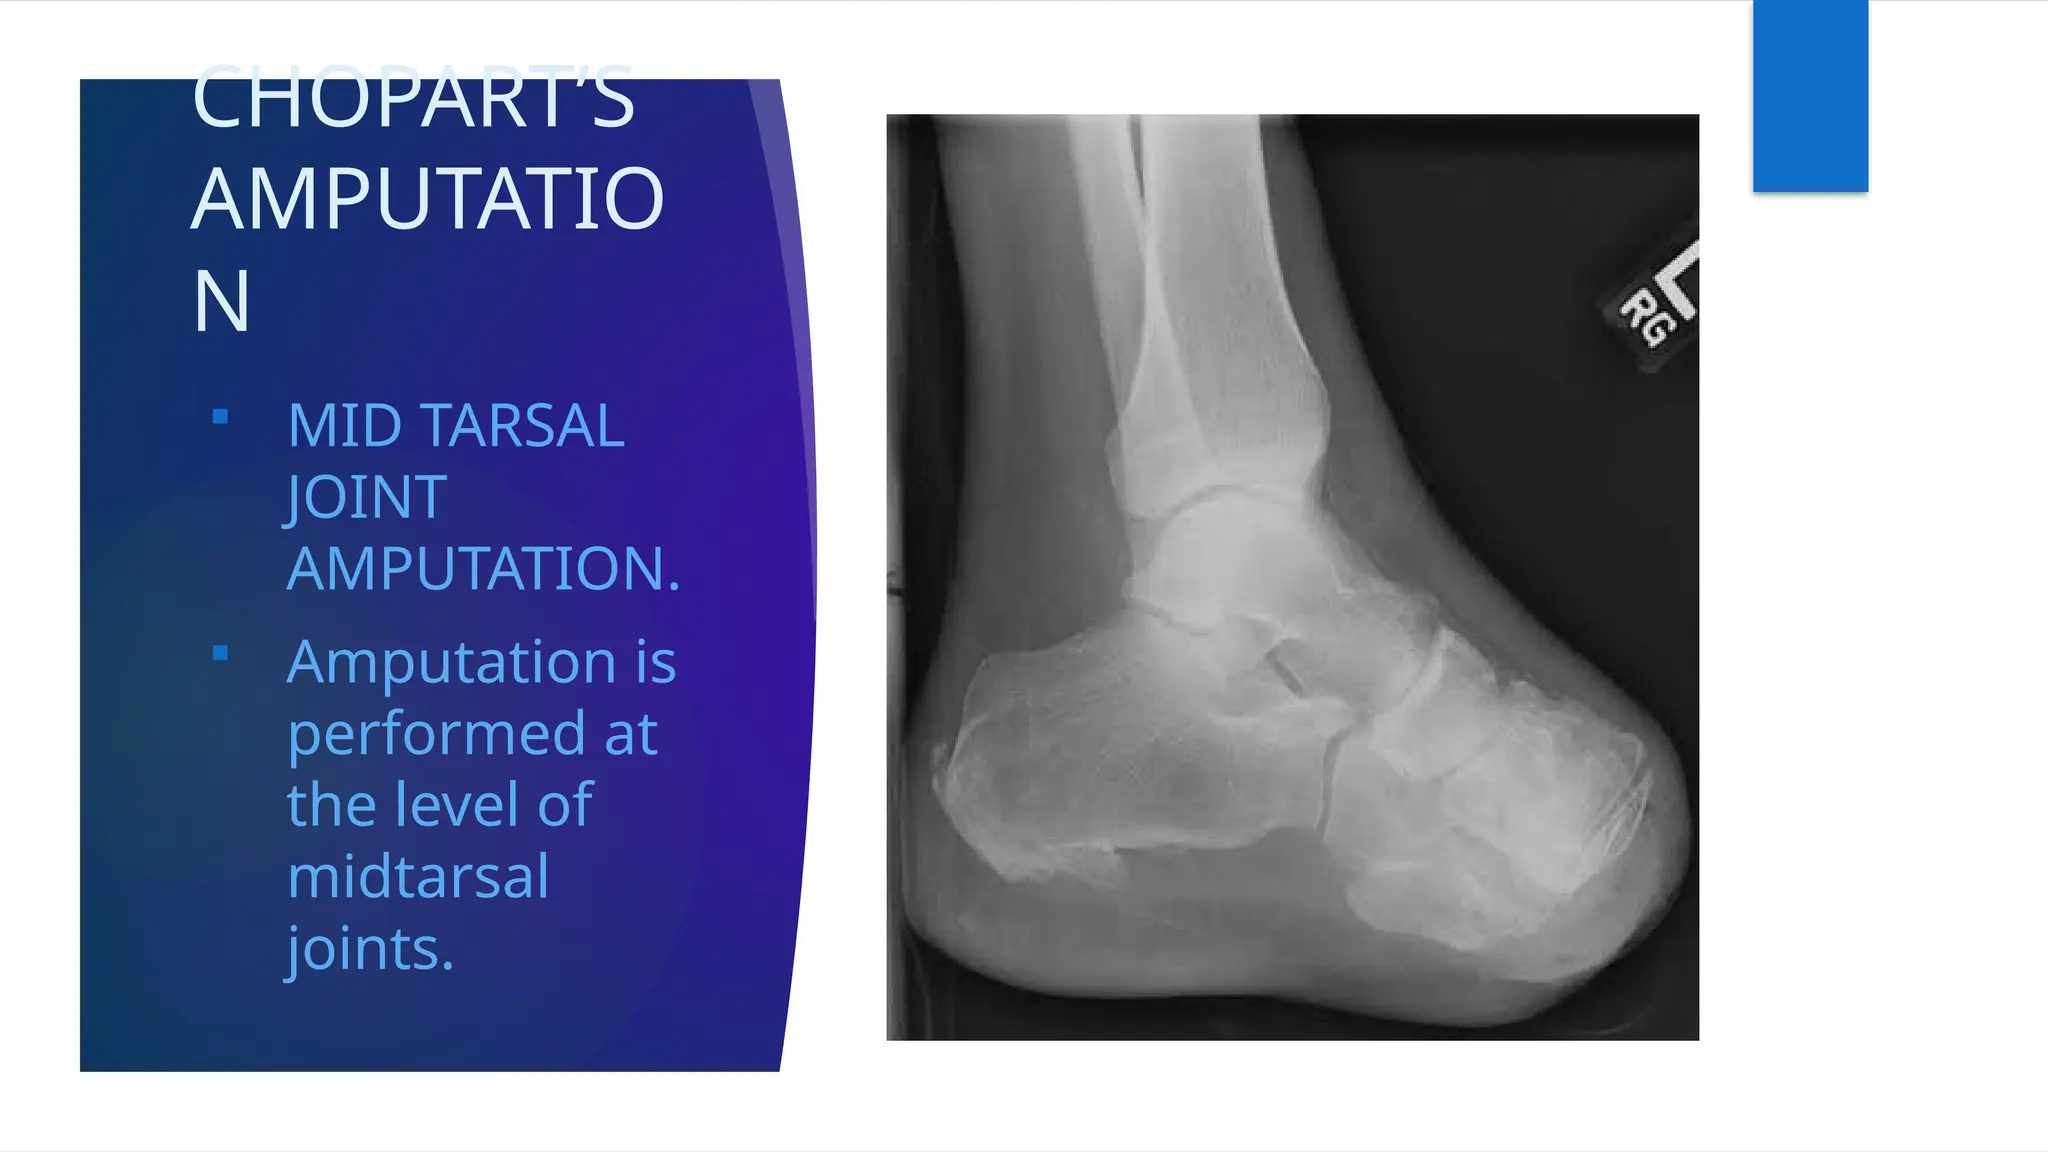

CHOPART’S

AMPUTATIO

N

 MID TARSAL

JOINT

AMPUTATION.

 Amputation is

performed at

the level of

midtarsal

joints.

CHOPART’S AMPUTATIO N  MID TARSAL JOINT AMPUTATION. Amputation is performed at the level of midtarsal joints.